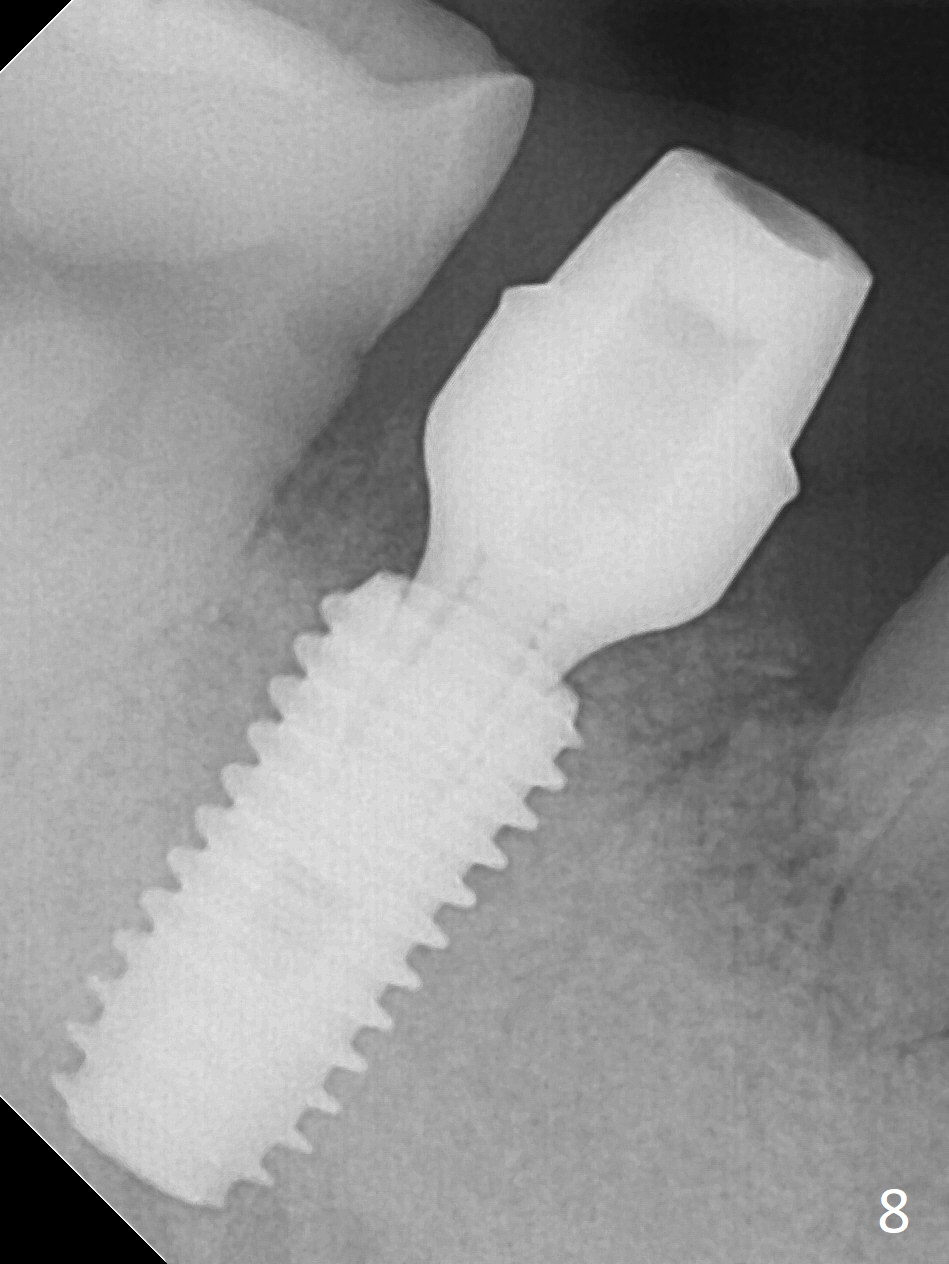

Although the tooth #30 has distobuccal root exposure (Fig.1 <), it is asymptomatic.  In contrast the tooth #31 with the distoocclusal caries (*) is symptomatic.  After use of 2 mm drill for 18 mm (lingual gingival margin), a calculated parallel pin is inserted (Fig.2 (D: 2 distal roots of the tooth #30)).  It appears that a 11.5 mm long implant is appropriate for the site; a 5 mm cuff is expected.  Following 4.8 mm drill, a 5.5x11.5 mm implant is placed initially (Fig.3) with an apical space (*) and clearance from the Inferior Alveolar Canal (red dashed line).  The implant is placed deeper with placement of a 6.5x4(5) mm abutment and bone graft (*, Fig.4,5).  After placement of collagen membrane over the graft, an immediate provisional is fabricated (Fig.6 P) with clearance from the opposing tooth (Fig.7 *).  There is no bone loss 3.5 months postop (Fig.8).  In fact the abutment has not been seated completely since its placement (Fig.4,5,8).  The crown/abutment dislodges 3 years 3 months post cementation (Fig.9).  The latter occurs for long incubation time because of opposing partial denture (Fig.10).  After trimming proximal surfaces (Fig.11: arrowheads), the abutment remains incompletely seated (Fig.11) due to possible crestal bone interference (Fig.11 *).  The smaller abutment by itself remains unseated (Fgi.12).  One size small one is completely seated (Fig.13).  Impression is taken.  Two weeks later the abutment margin is supragingival.  After screw torque at 20 Ncm, the crown is cemented with access hole.  Excess cement is removed.